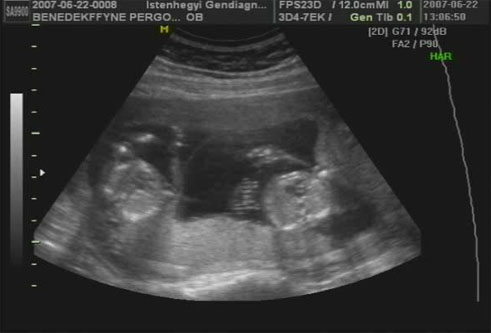

Megjöttünk a genetikairól!Fantasztikus élmény volt!Kb. egy hete olyan fura érzéseim vannak belül,mintha kiakarnák szakítani a méhem vagy mintha összerándulna egy csomóvá!Hát megvannak a kis bűnösök!Ők ficánkolnak annyit,hogy a doki alig tudta lemérni őket!Egyébként mindenük megvan és édesek, makk egészségesek!A fiú 325gr,a lány 300 gr.Minimális eltérések vannak,de teljesen jó,sőt 20+1 napsnak felelnbek meg a 19+5 helyett,de ez lófütty!

Szóval a doki befogta az a rcát UH-val és elfordult,hogy bejelölje,addigra a fiú a fenekét dugta oda!Azt mondta ha ezt nem látja,akkor el sem hiszi,olyan ramazuri van benn és nagyon sajnál amiért még ilyen sook van hátra és ennyi ficergéssel!Szóval csajok annyit mozognak,hogy egy percig sem álltak meg a fél óra alatt!De egyik sem!Mi lesz ha kibújnak?Akkora ficergés van,hogy iszonyatosan keményedik miattuk a pocakom!Ja,hát arról nem is beszélek,ők hogyan gyepálják egymást,pedig van közöttük egy burok!!!!

Nekem is a doki mondta hogy legközeleb a 28.héten menjünk 4D-re!Képet sajna nem tudott csak oldalról csinálni,mert mindkettő befúrta az arcát és magát a méhlepénybe!Na meg nem lehetett őket befogni,mert annyit mocorogtak,hogy semmi nem látszik belőlük.Viszont egy ismerősöm a dvd-ből kiválaszt valahogy képeket és azokat előhívatjuk,majd azt felteszem!A 14.hetiről már van egy kis albumnyi! Kép

A második képen a lányok szíve látható az én kis tökösömnek!

Gyönyörűek ezek a lányok és hogy te milyen vékonyka vagy!Szépek vagytok!Az UH 06.22-én készült még,de majd rakok fel frisseket is,csak ahhoz szakember ismerős kell,mert ő tud DVD-ről képeket leszedni,utána meg előhívatom majd a Camponában!